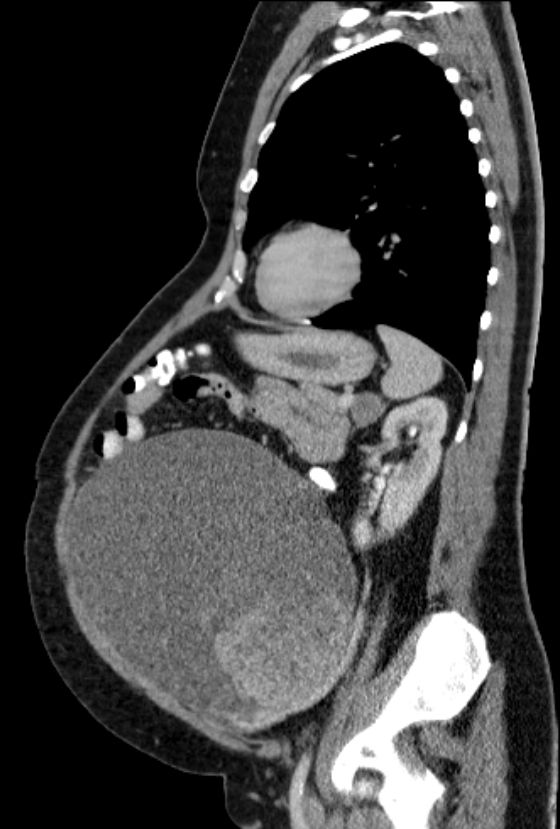

53-jährige Frau mit einem muzinösen Borderlinetumor vom intestinalen Typ.